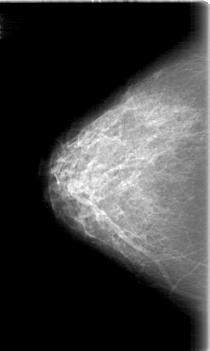

D_4058_1.RIGHT_CC

RIGHT_CC LINES 5251 PIXELS_PER_LINE 3136 BITS_PER_PIXEL 12 RESOLUTION 43.5 NON_OVERLAY